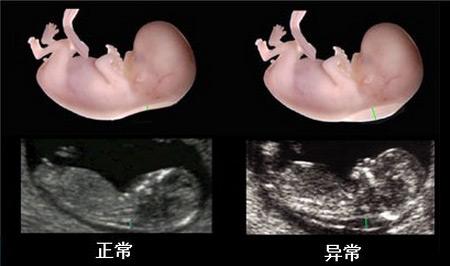

NT即nuchal translucency的缩写,它指的是“颈项透明层”,也就是胎儿颈椎水平矢关切面皮肤至皮下软策划之间的最大厚度。NT检查也是早期唐氏筛查的诊断依据之一,检查目的是为了在妊娠较早阶段诊断染色体疾病和发现多种原因导致的胎儿异常。通过彩色超声检查胎儿的颈椎厚度,是排除胎儿畸形的一种常规检查!如果检查结果超过3mm,常提示有不良胎儿结局。需要重点记录,便于在后期的唐氏筛查(16-18周)和四维彩超(24周)排挤检查时提示医生重点关注。

NT筛查是通过B超测胎儿颈部透明带厚度。颈部透明带是指胎儿颈部后方皮下积水的空隙,进行超音波扫描时,医师会详细测量介于皮肤和策划之间的空隙厚度,染色体异常的胎儿,其颈部透明带会明显增厚,特别是唐氏症儿。通常唐氏症较易发生在高龄产妇身上,医学文献已证实当胎儿后颈部透明带越厚,染色体异常的机率就越高。